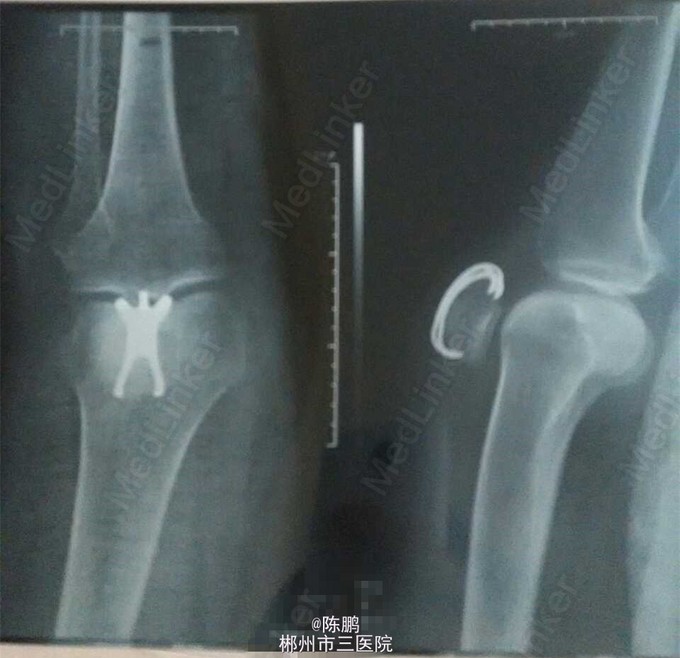

初步诊断:右髌骨骨折 在腰麻下行右髌骨骨折开放复位髌骨爪内固定术

髌骨爪适用范围 是供髌骨各类骨折外固定用的手术器械。产品禁忌症:1.金属过敏者禁用。2.老年人、骨质疏松、糖尿病等不宜骨科手术的患者慎用。